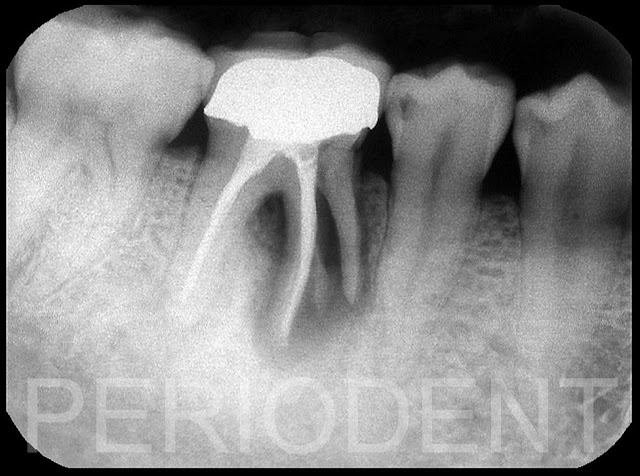

陳柏堅醫師發表右下拔牙後齒槽骨嚴重垂直凹陷之處理-1

患者因為牙根分叉處之處理斷裂及牙周病,拔除右下兩顆大臼齒